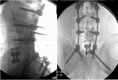

Traumatic L5 Posterolateral Spondyloptosis: A Case Report and Review of the Literature

Traumatic retrolisthesis of the lumbar spine is a rare clinical entity. Only a few case reports have shown retrolisthesis of the fractured fragment over the inferior vertebral body. Fracture dislocations of the spine are unstable injuries that require operative fixation to restore alignment and prevent progressive deformity. We present the case of a traumatic L5-S1 fracture dislocation with retrolisthesis of the L5 vertebral body over the superior aspect of S1 managed with anterior, middle, and posterior column reconstruction. The patient presented with paraplegia and bowel and bladder incontinence. Retrolisthesis fracture dislocations injuries are rare, and as such, there are no guidelines regarding their management. In our case, we performed an L5 vertebrectomy with anterior, middle, and posterior column reconstruction via a posterior approach using a lumbosacral-pelvic construct. The patient did not regain function in his distal lower extremities postoperatively.